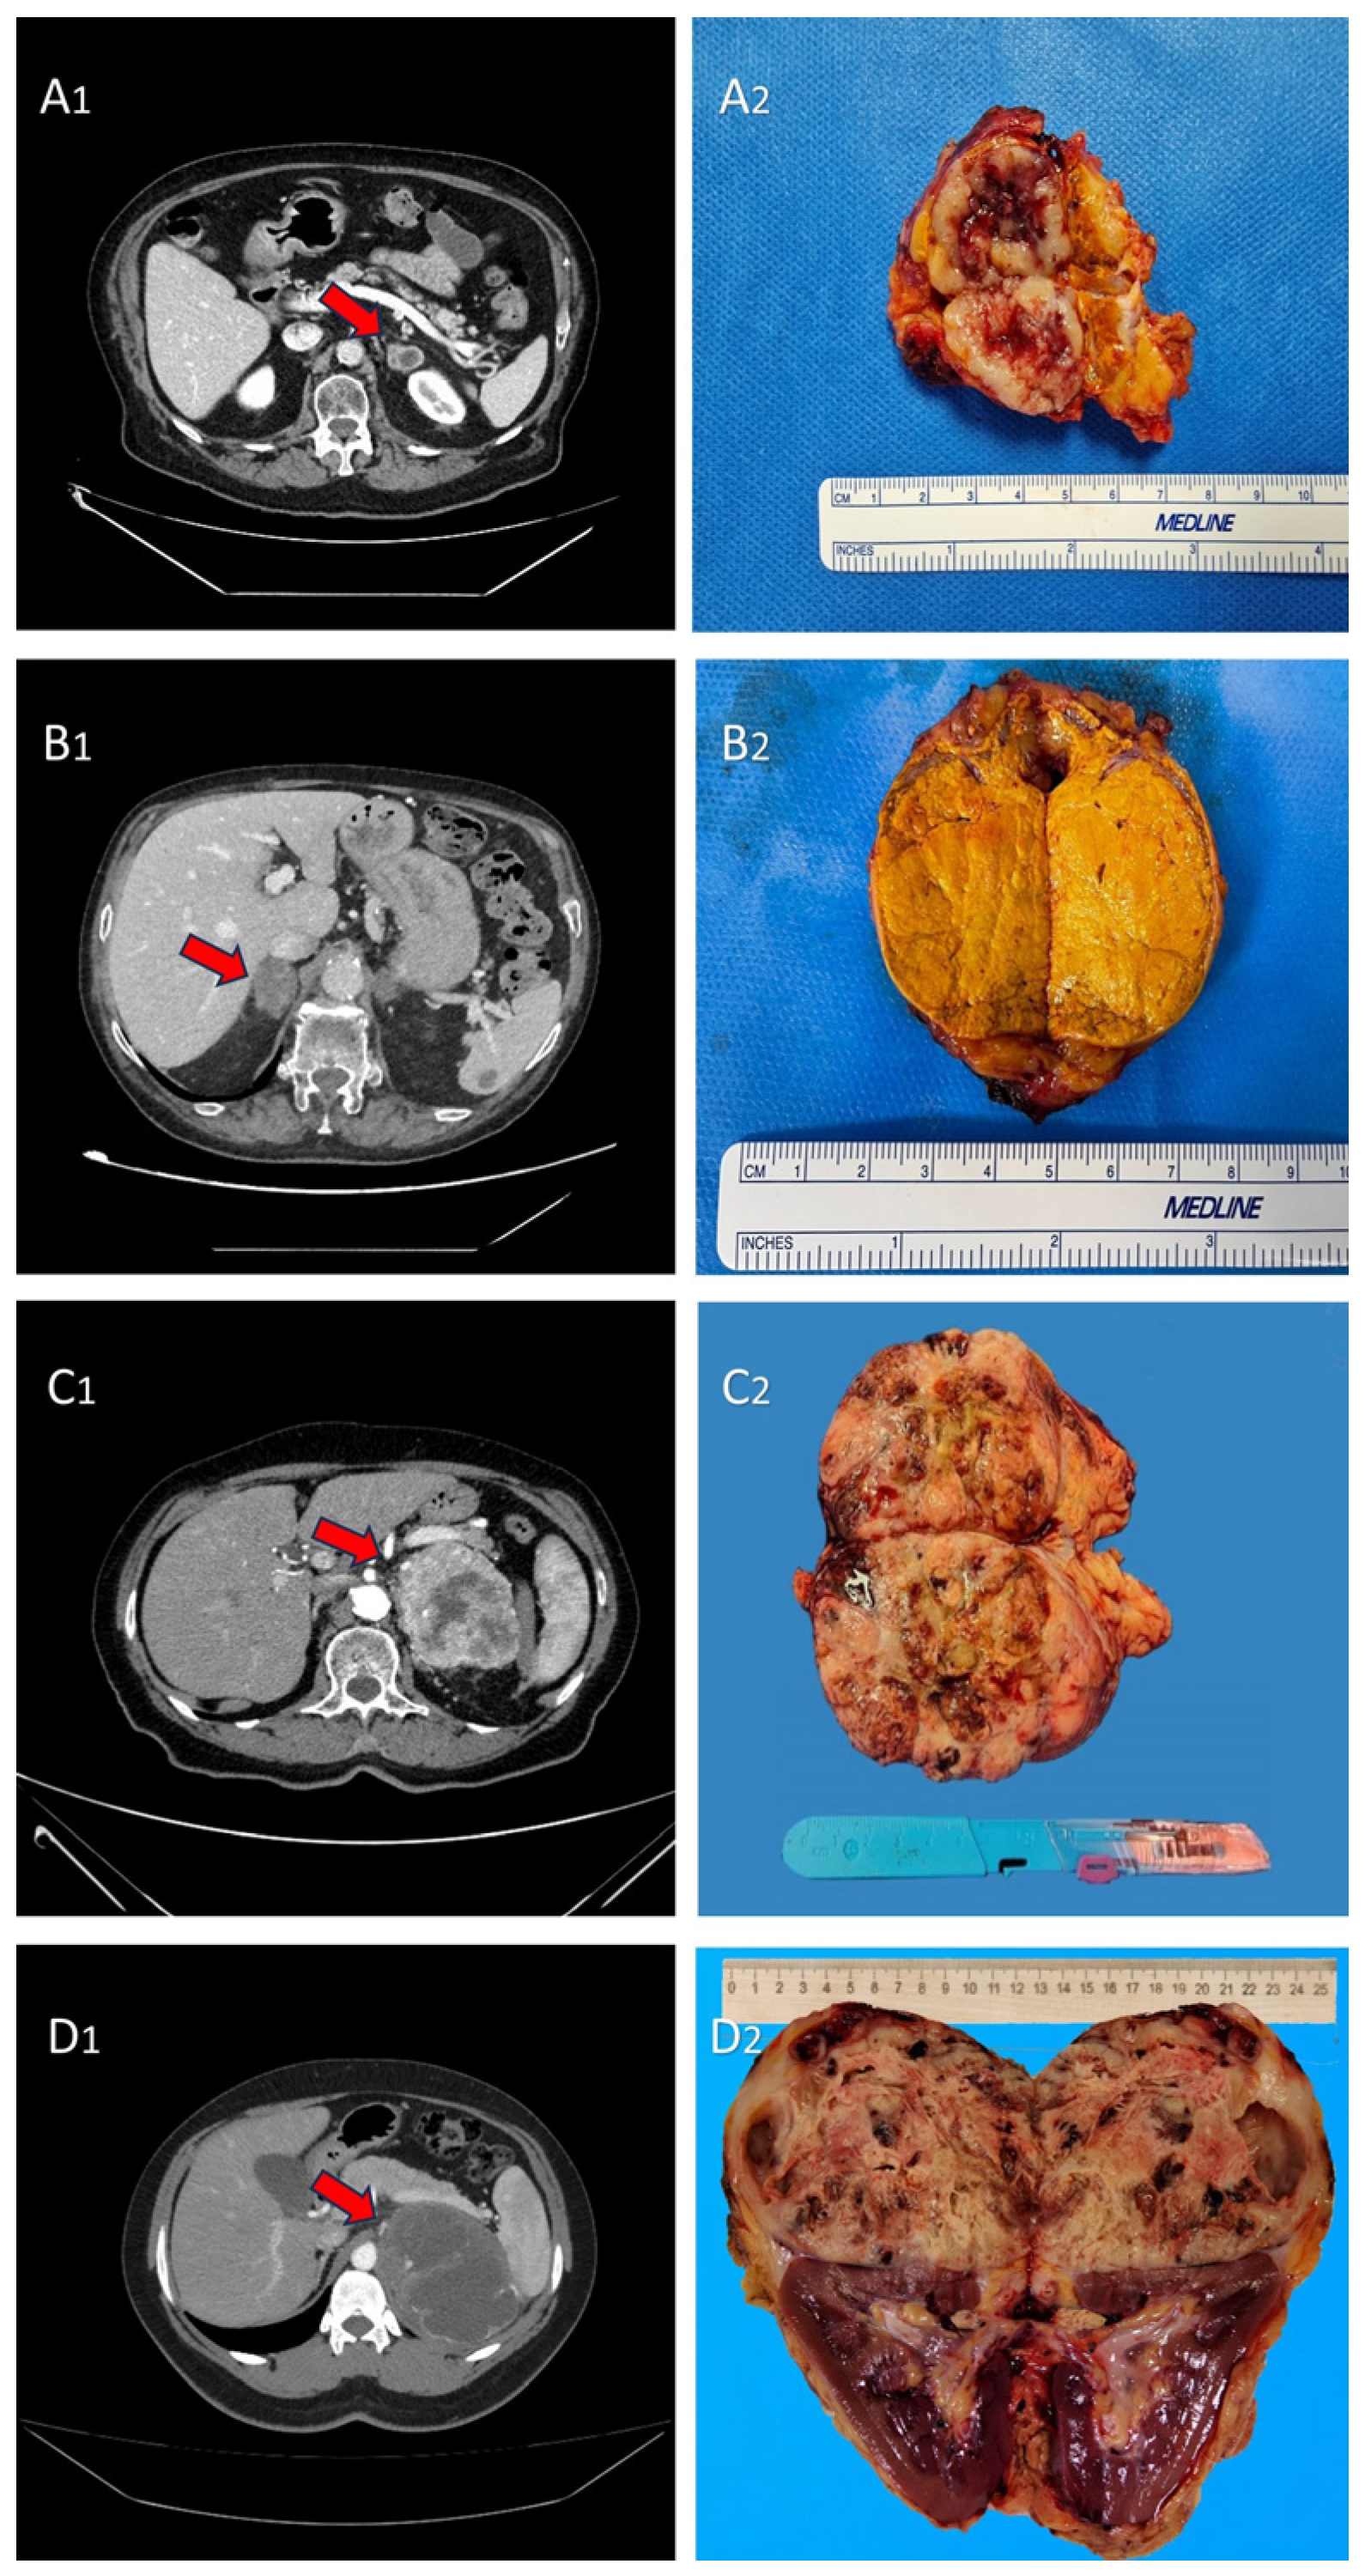

2.2. Surgical Technique